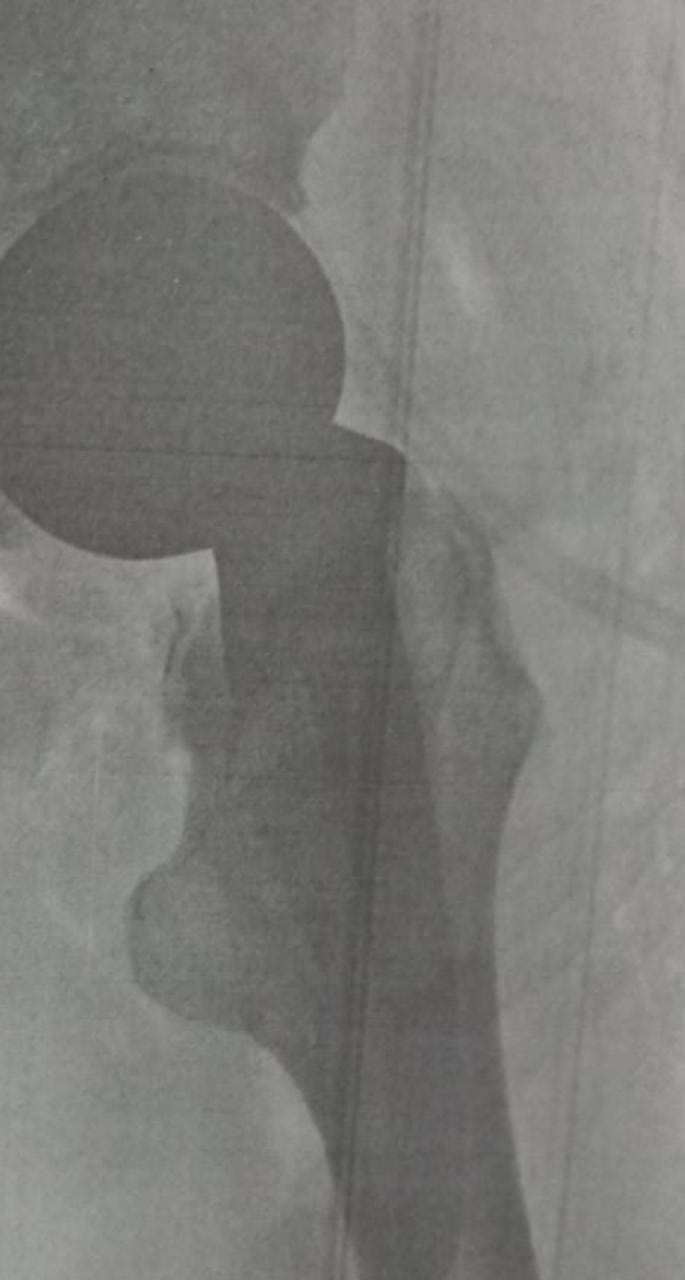

أشاد اللواء هشام آمنة  محافظ البحيرة بجهود و نجاح فريق قسم جراحة العظام بمستشفي ادكو المركزي  في زراعة نصف مفصل صناعي لمريض مسن يبلغ من العمر 68 عاما  كان يعانى من كسر  بمفصل الفخذ  الأيسر وعجز عن الحركة.

حيث قام الفريق الطبي بمستشفى ادكو بقيادة د عبدالحميد الطيباني  مدير المستشفى و د  حسن معوض زيتون -  استشاري ورئيس قسم العظام بالمستشفى و د عماد رياض  طبيب مقيم عظام و د عبدالرحمن عيسى -  استشاري التخدير تحت إشراف أ.د محمود طلحة .وكيل الوزارة ود حمودة الجزار - وكيل مديرية الصحة بإجراء العملية وتم إعادة تركيب نصف مفصل من نوع خاص يلائم حالة المريض.